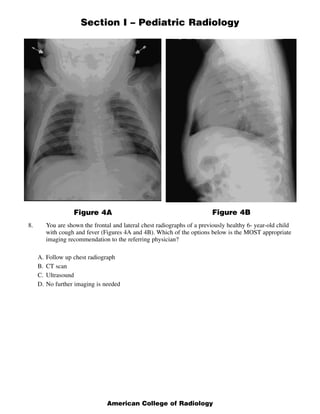

This document contains a multiple choice question and rationales from a pediatric radiology exam. The question shows MRI images of a 22-week fetus and asks for the most likely diagnosis. The rationales eliminate the other answer choices of posterior urethral valves, multicystic dysplastic kidneys, and bilateral ureteropelvic junction obstruction. The correct answer is Autosomal Recessive Polycystic Kidney Disease, as the images show enlarged, fluid-intensity kidneys without urine production, typical of this condition.